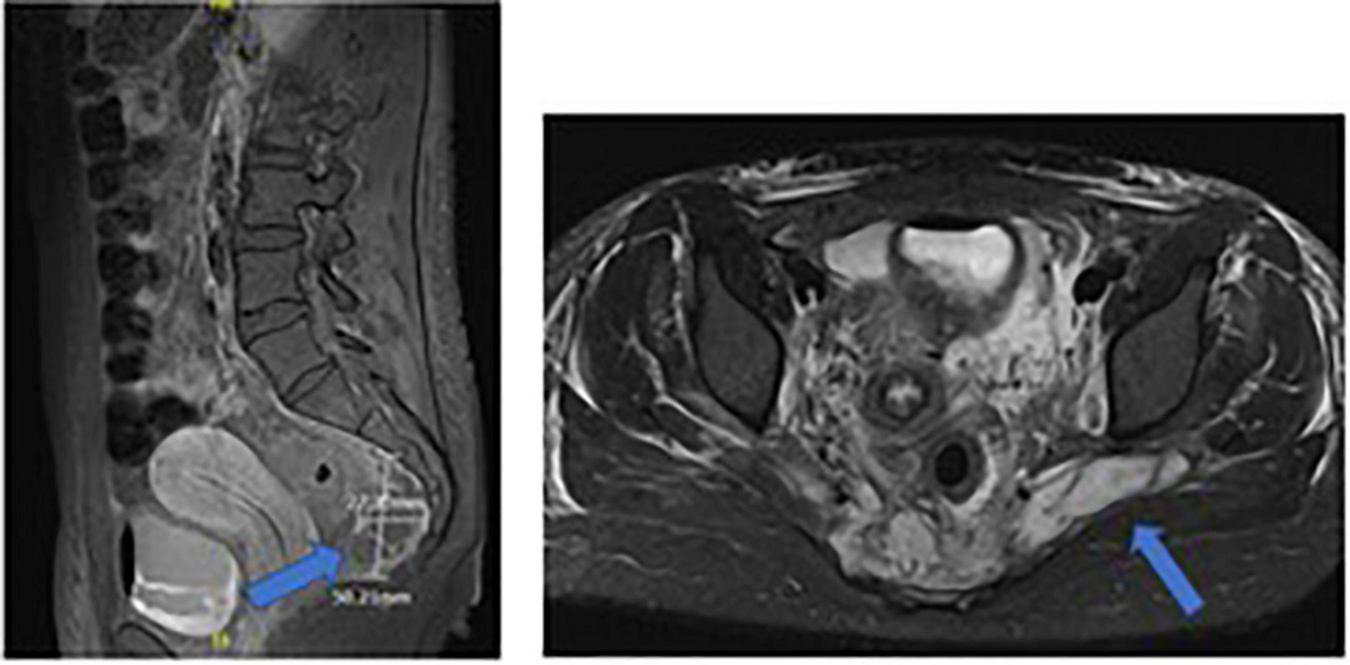

At admission to PICU, a pancarditis with endocarditis of the mitral valve apparatus and pericardial effusion were highlighted. The extended workup showed cerebral, pulmonary, renal, and cutaneous emboli. An MRI of the pelvis, performed because of the history of coccygeal pain, revealed sacral osteomyelitis and multiple adjacent abscesses (Figure 3). Therefore, the suspected mechanism of septic shock was endocarditis with multiple emboli secondary to sacral osteomyelitis.

FIGURE 3

Sacral MRI of case 3: sacral osteomyelitis and multiple adjacent abscesses.